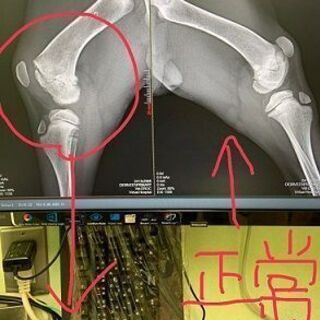

脱臼と靭帯損傷で病院へつれていきました。靭帯損傷は治るとおもいます。

レントゲンの結果、後ろ足のおさらが骨とくっついていないことが判明。先天性の可能性もあります。成長過程で治らない場合は成犬になってから手術が必要になるかもしれません。

おさらがくっつかない場合大きくなってから手術が必要になる可能性がゼロではありません。